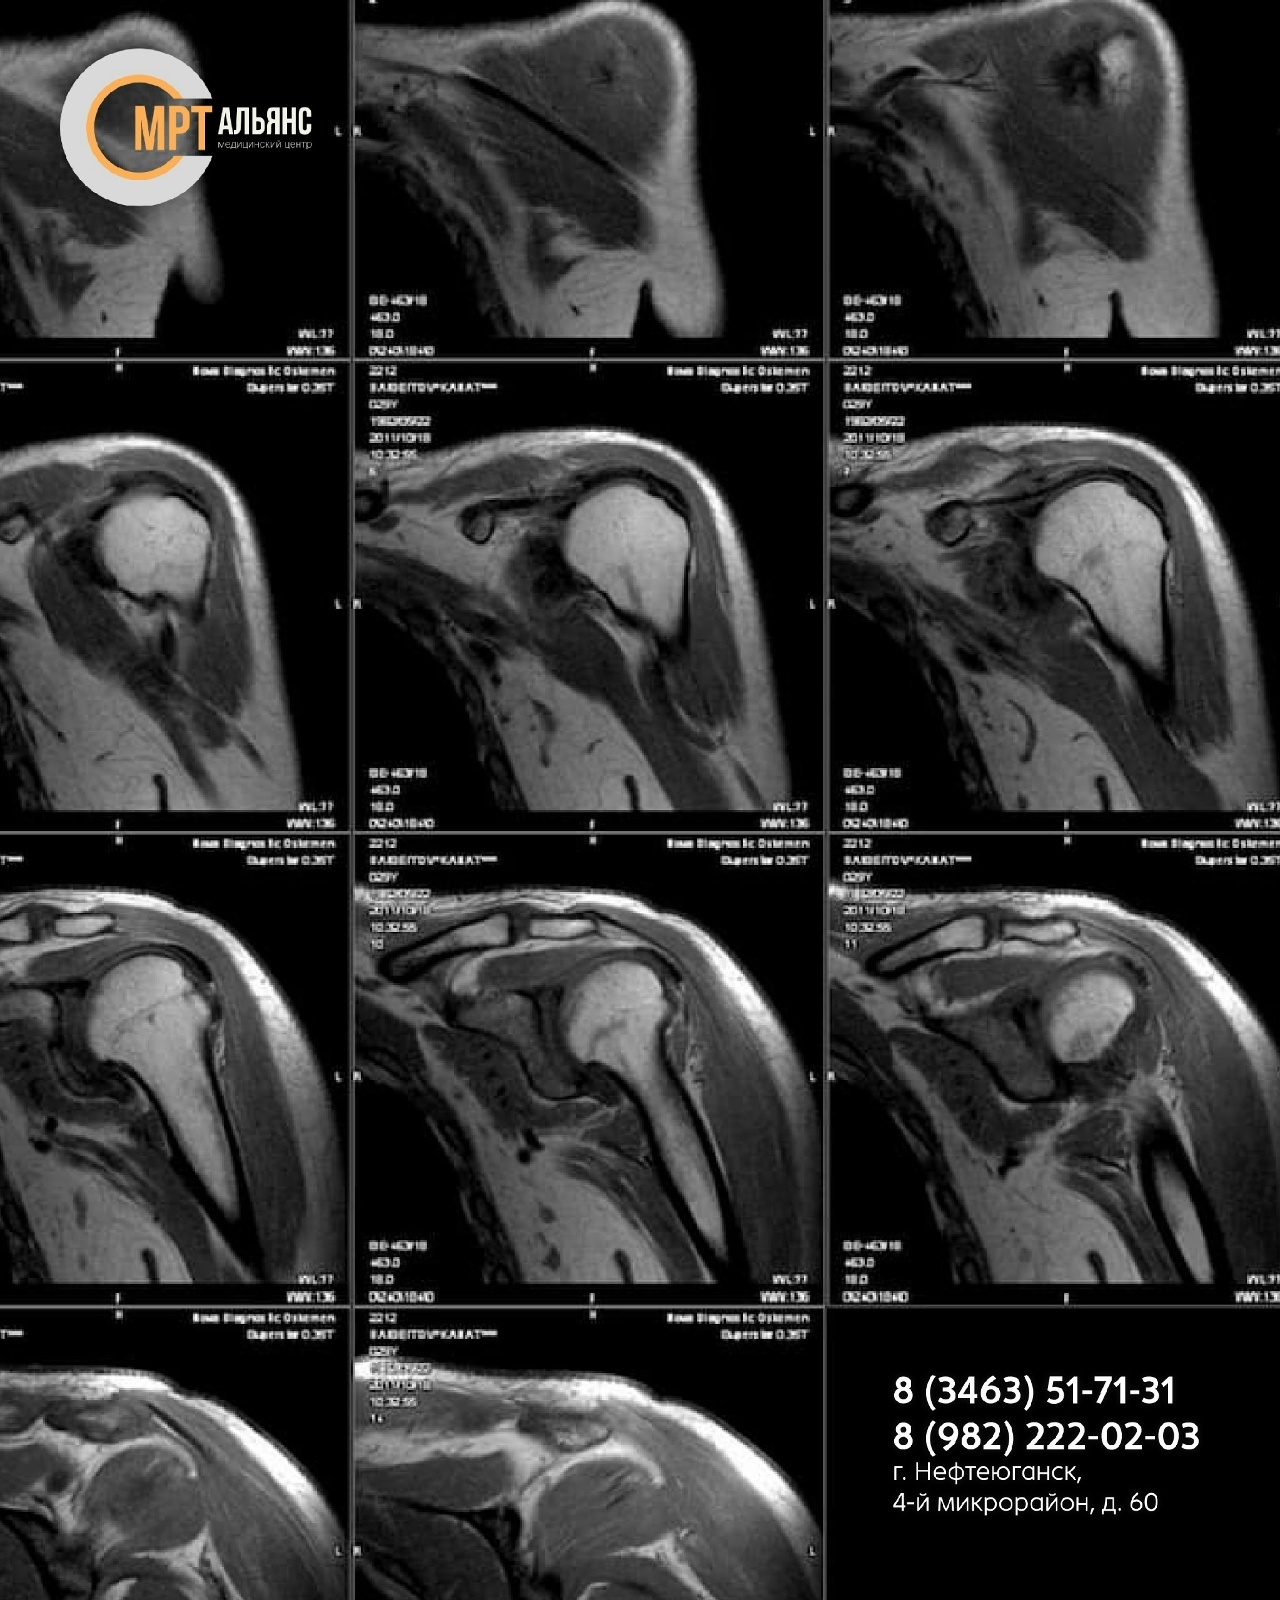

Испытываете боль, скованность или дискомфорт в плече? Причина может быть скрытой. Магнитно-резонансная томография — это золотой стандарт детальной диагностики, который визуализирует ткани послойно с точностью до 1 мм.

Мы всесторонне оцениваем состояние:

• Мягких тканей (мышцы, связки)

• Сосудов

• Костных структур

• Нервных корешков

Что мы выявляем:

• Воспаления, опухоли, микротрещины хрящей

• Сдавливание сосудов, последствия травм, патологии суставов (артрит, тендинит, бурсит)

• Скрытые повреждения после ушибов и подвывихов

Исследование проводится при подозрении на широкий спектр патологий: инфекционные, аутоиммунные, травматические, воспалительные и другие